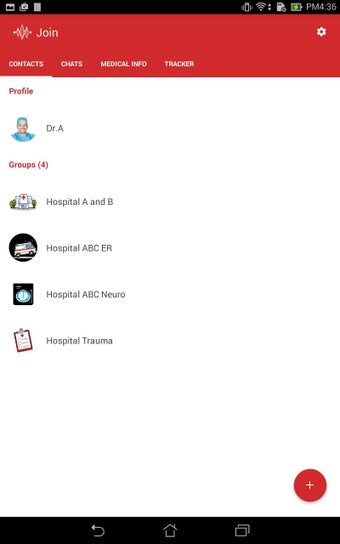

Join adalah aplikasi berbasis awan yang digunakan oleh para profesional dan penyedia layanan kesehatan untuk berkomunikasi secara aman dan berbagi informasi pasien. Aplikasi ini telah dikembangkan oleh perusahaan kami, dan dapat digunakan bersamaan dengan sistem catatan medis elektronik yang kompatibel (EMR atau EMR*).

Untuk memberikan perawatan terbaik bagi pasien, para profesional kesehatan perlu memiliki akses cepat dan mudah ke riwayat medis pasien, termasuk data laboratorium, resep obat, dan laporan radiologi. Dengan Join, mereka dapat dengan mudah mengirimkan gambar rekam medis pasien kepada rekan mereka, sehingga mereka dapat dengan cepat dan efisien membuat diagnosis dan rencana perawatan.

Join juga memungkinkan mereka untuk berkomunikasi dengan rekan mereka tentang kondisi pasien, yang sangat penting untuk memberikan perawatan terbaik.